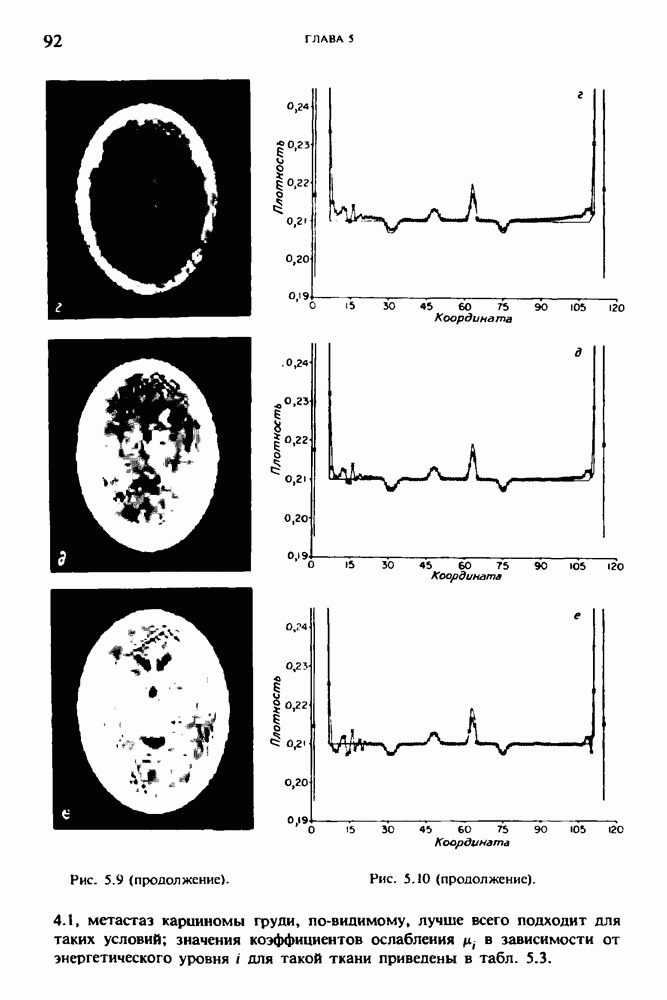

15.5. ЭКСПЕРИМЕНТАЛЬНЫЕ РЕЗУЛЬТАТЫ

Наш первый пример относится к случаю отображения системы желудочков головного мозга человека, которое было сделано по восьми смежным срезам толщиной На рис. 15.1 (вверху) приведены фрагменты из 80 х 80 элементов изображения трех из указанных срезов. Система желудочков изображена на фрагментах полностью. Размер элемента изображения в срезах составлял 1,5 х 1,5 мм, что соответствовало размеру элементарного

объема 1,5 х 1,5 х 8 мм, хотя более желательна, как и в предыдущих разделах, была бы кубическая форма элементарных объемов. Чтобы преобразовать элементарные объемы в кубические, использовалась линейная интерполяция данных для оценки 38 смежных срезов толщиной 1,5 мм. Таким образом, формируется массив из 80 х 80 х 32 чисел, характеризующих среднюю плотность множества элементарных объемов кубической формы.

Причина, по которой желудочки мозга выглядят более темными, чем окружающие ткани, состоит в том, что они содержат спинномозговую жидкость с несколько меньшим, чем у мозга, линейным коэффициентом ослабления (табл. 4.1). Поэтому диапазон значений, введенный в разд. 15.1, оказался таким, что его верхний предел стал больше, чем линейный коэффициент ослабления цереброспинальной жидкости, но меньшим, чем для самого мозга. Последнее означает, что все элементарные объемы, характеризующие спинномозговую жидкость, имеют числа Хаунсфилда в указанном диапазоне Таким образом, множество элементарных объемов, в которых числа Хаунсфилда лежат в диапазоне (разд. 15.2), содержит не только области желудочков, но также и другие части мозга, либо заполненные спинномозговой жидкостью, либо не заполненные ей, но имеющие по разным причинам такие же числа Хаунсфилда в данном диапазоне, например, вследствие наличия шума в исходных данных, артефактов при реконструкции и т.д. Элементарные объемы, которые принадлежат множеству изображены в виде светлых областей в нижней части рис. 15.1. Анатомическая картина соответствующих частей системы желудочков, показывающая в том числе положение corpora quadragemina («четверохолмие»), приведена на рис. 15.6.